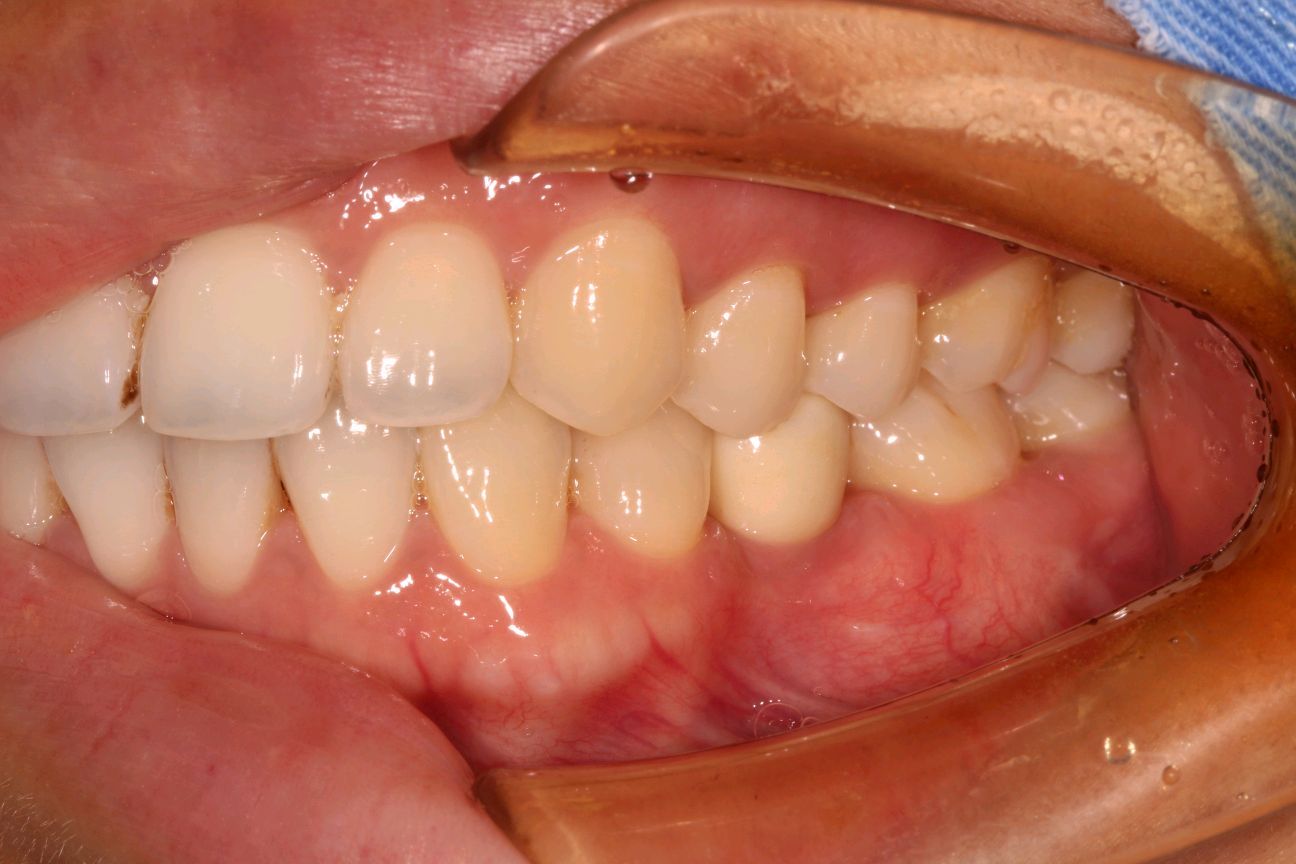

患者女三十岁,35畸形中央尖折断,根尖周炎症感染,导致牙根发育停止,根尖口呈喇叭口状。拔出后搔刮牙槽窝,颊侧骨壁吸收,植入骨粉骨膜。定期复查,将近半年见骨密度良好,骨量充足的条件下,行种植手术。植入3I 4/3*11.5mm的种植体。二期三期如期进行,与今日戴牙,患者满意。

二期术后